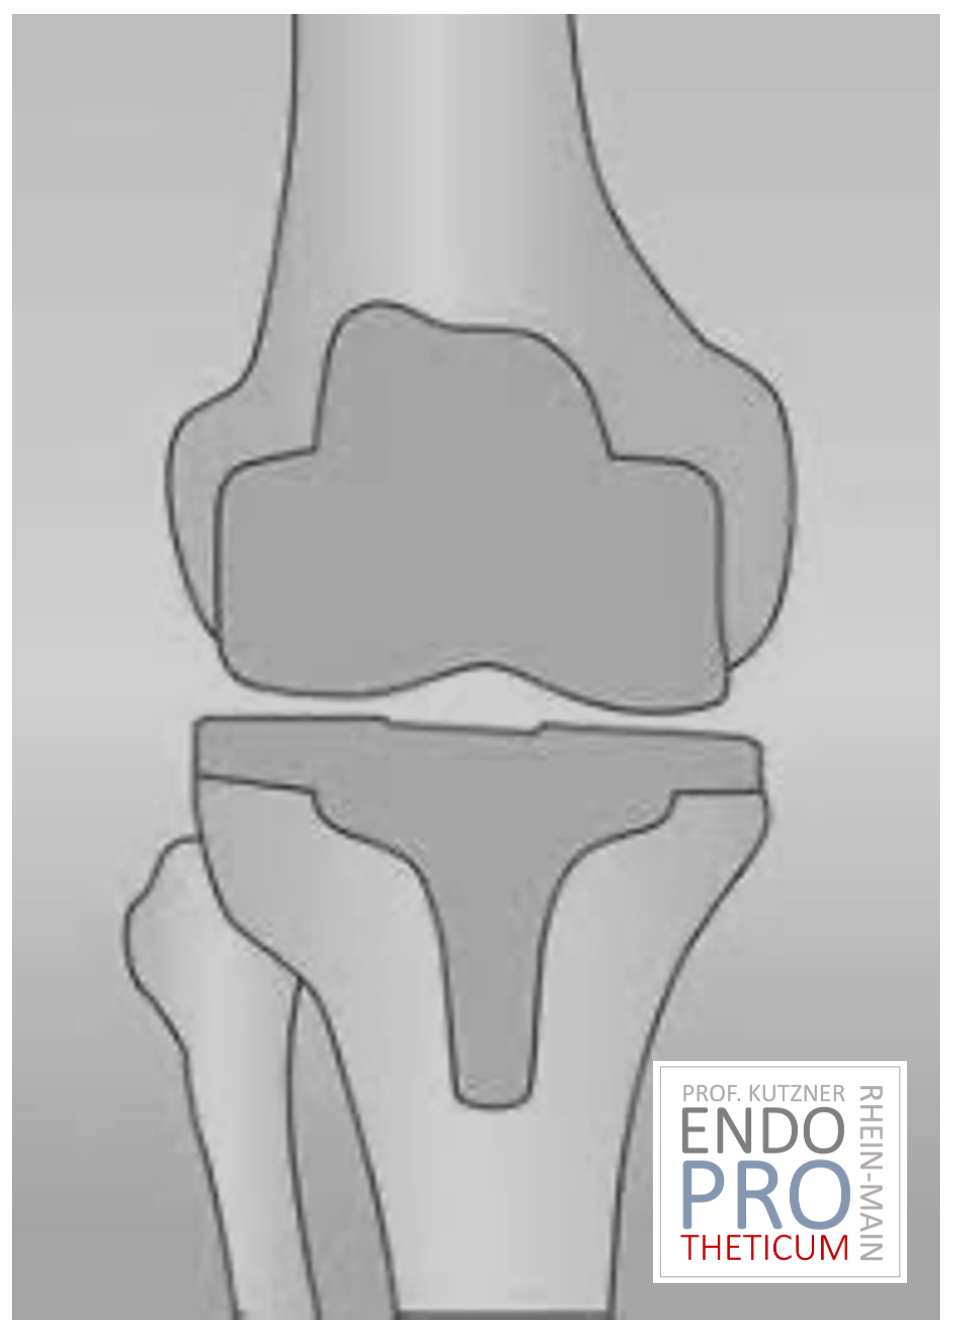

La articulación de rodilla artificial reemplaza la superficie del cartílago destruida por la osteoartritis. El hueso subyacente del fémur y la cabeza tibial permanece intacto. Algunos comparan una articulación artificial moderna de rodilla con la coronación de un diente; el término exacto es el llamado rejuvenecimiento bicondilar. Entre las nuevas superficies de la parte superior e inferior de la pierna se encuentra la llamada incrustación de un plástico blanco especialmente endurecido, que en la imagen de rayos X se puede ver como la distancia entre las piezas metálicas.